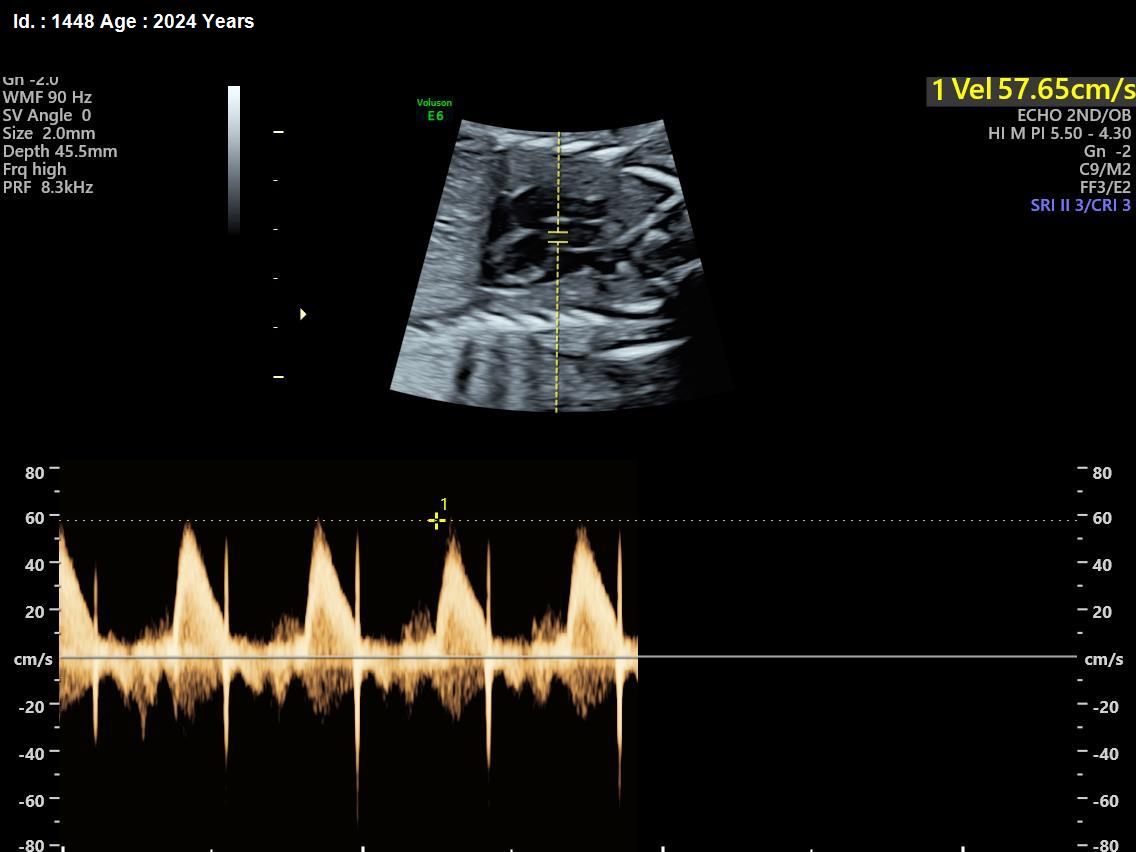

It is a test similar to ultrasound. It allows the doctor to see structure and function of the baby’s heart in detail. It also enables the doctor to see blood flow through fetal heart and cardiac rhythm. The scan is done by a radiologist or a fetal medicine specialist.

A fetal echocardiogram focuses specifically on the fetal heart, providing a detailed examination of its structure and function. In contrast, a standard ultrasound assesses overall fetal development and growth.